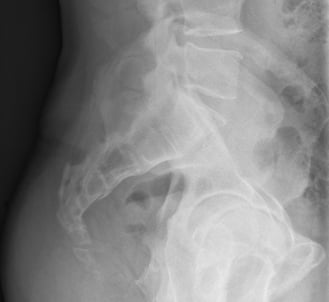

Not a simple X-ray

Sitting versus standing radiographs should be performed after 10 minutes of standing to make sure that the coccyx is in a neutral position. The sitting radiograph should be performed on a hard stool with the patient having a straight back, and thighs horizontal (you might need a footrest), and the seated radiograph performed on a hard stool. When seated, the patient should start with a flat back, thighs horizontal, and then they should lean back to the point of maximum tenderness before the X-ray is obtained.